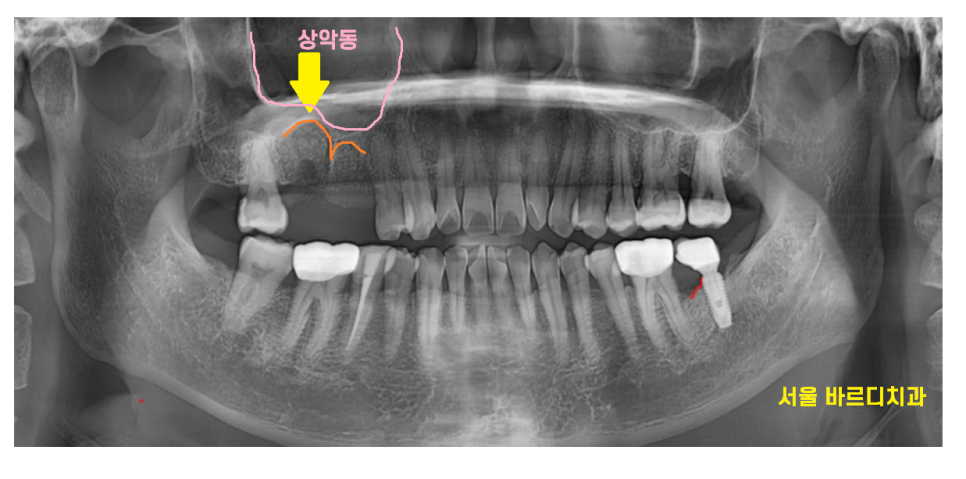

맨 처음 방문하셨을 때 사진입니다.

23.03.20

계속된 잇몸 뾰루지로

염증이 치아 주변 뼈를 녹였네요.

심지어 치아 뿌리가 일부 흡수된 모습까지 관찰